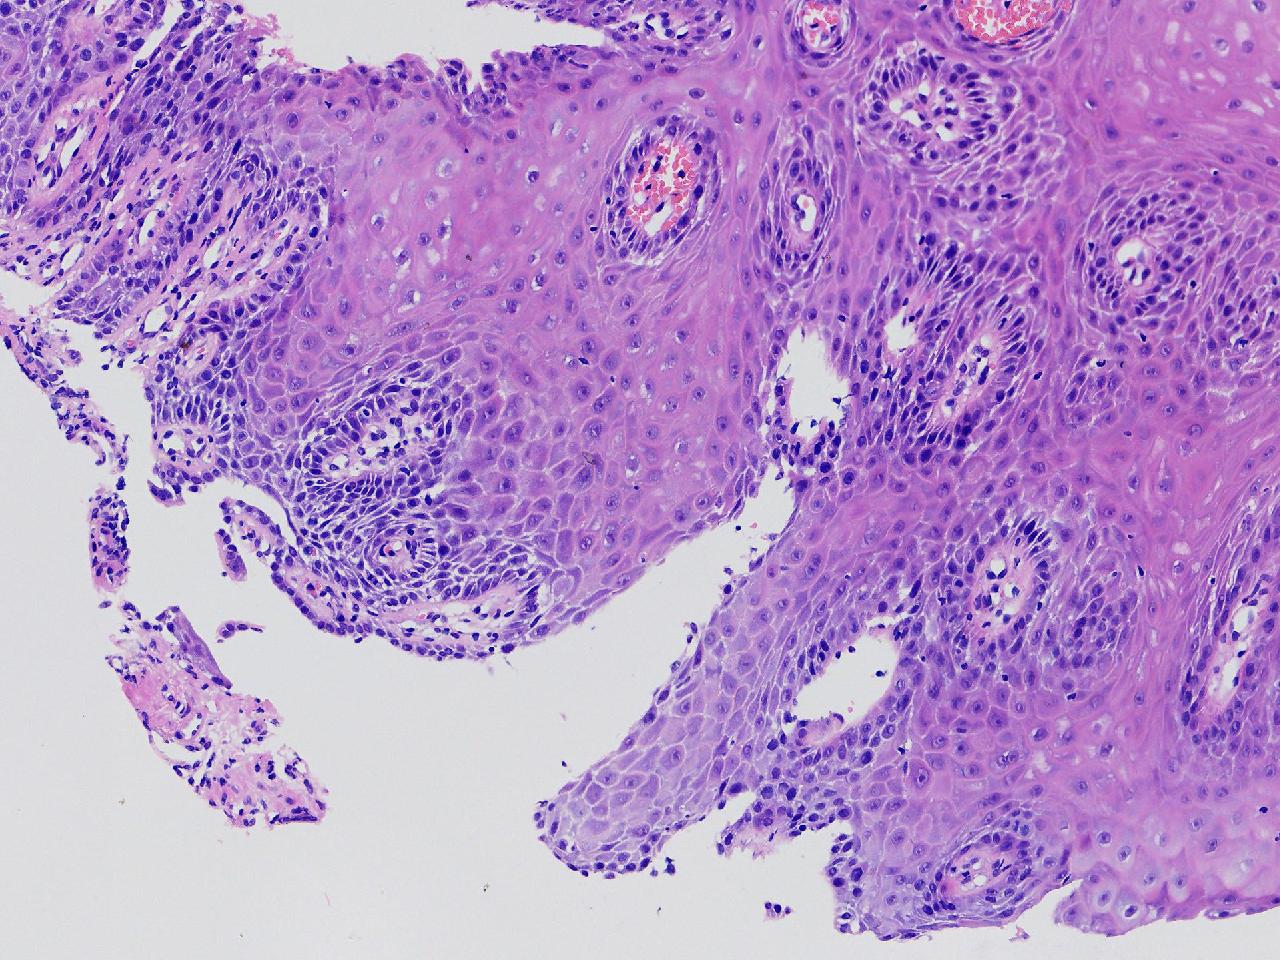

男,62岁,贲门口齿状线上见条状糜烂,活检1块,质软。

贲门口活检

灰白色不整形软组织1块,直径0.2厘米。

图1

鳞皮乳头状增生伴慢性炎。